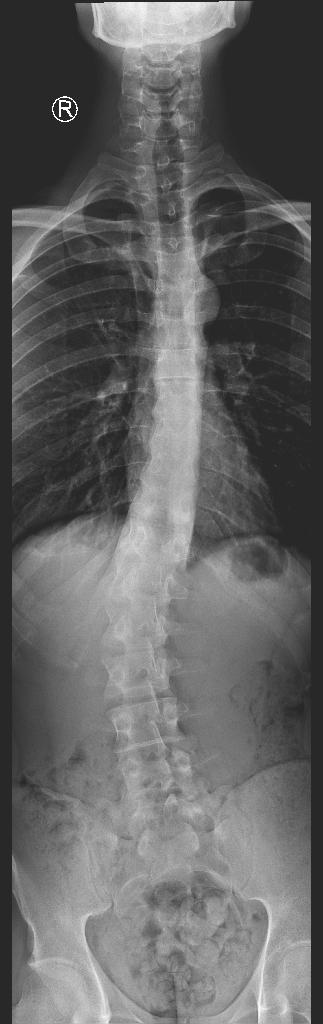

Got my x-rays done and turns out that I'm already withering away in muh 20s. Have mild osteochondrosis and have some osteophytes developing on my lower vertebrae. 15 degree lumbar scoliosis btw.

File: Image.jpg (37 KB, 323x1024)

37 KB

37 KB JPG

>>77099572

Milk doesnt do shit if you sit your ass all day on a chair. Pic rel my Xrays at 25 when i realised that something's fucked up and i should start working out.

>>77103833

Why spine bendy?